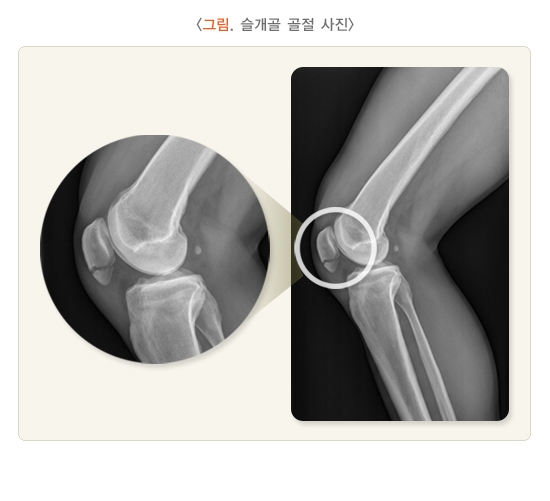

2. 슬개골 골절

슬개골 골절은 대부분 대퇴슬개 관절면을 침범하는 관절 내 골절의 형태로 발생하며, 관절면의 층 형성이 2mm 이상이거나 골절편(골절 조각)의 전위가 3mm 이상인 경우 수술적 치료가 필요합니다. 보존적 치료가 가능한 경우엔 원통형 또는 장하지(긴다리) 석고 고정을 시행한 후 슬관절 경첩 보조기를 착용하거나, 처음부터 보조기를 착용할 수 있습니다. 수술적 치료를 시행할 경우에는 나사못, 강선 등을 사용하여 고정하거나, 부서진 정도가 너무 심한 경우 골절편 제거 등을 시행 할 수 있습니다.